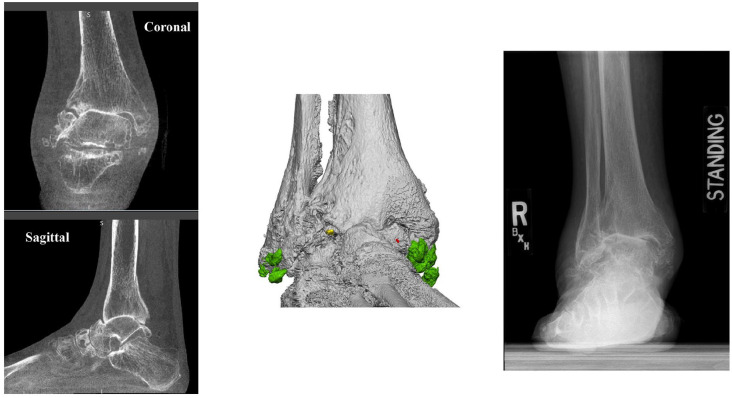

Abstract Image